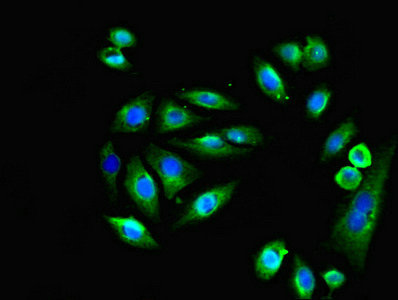

應用范圍:ELISA, IHC, IF

Application Recommended Dilution IHC 1:20-1:200 IF 1:50-1:200 -